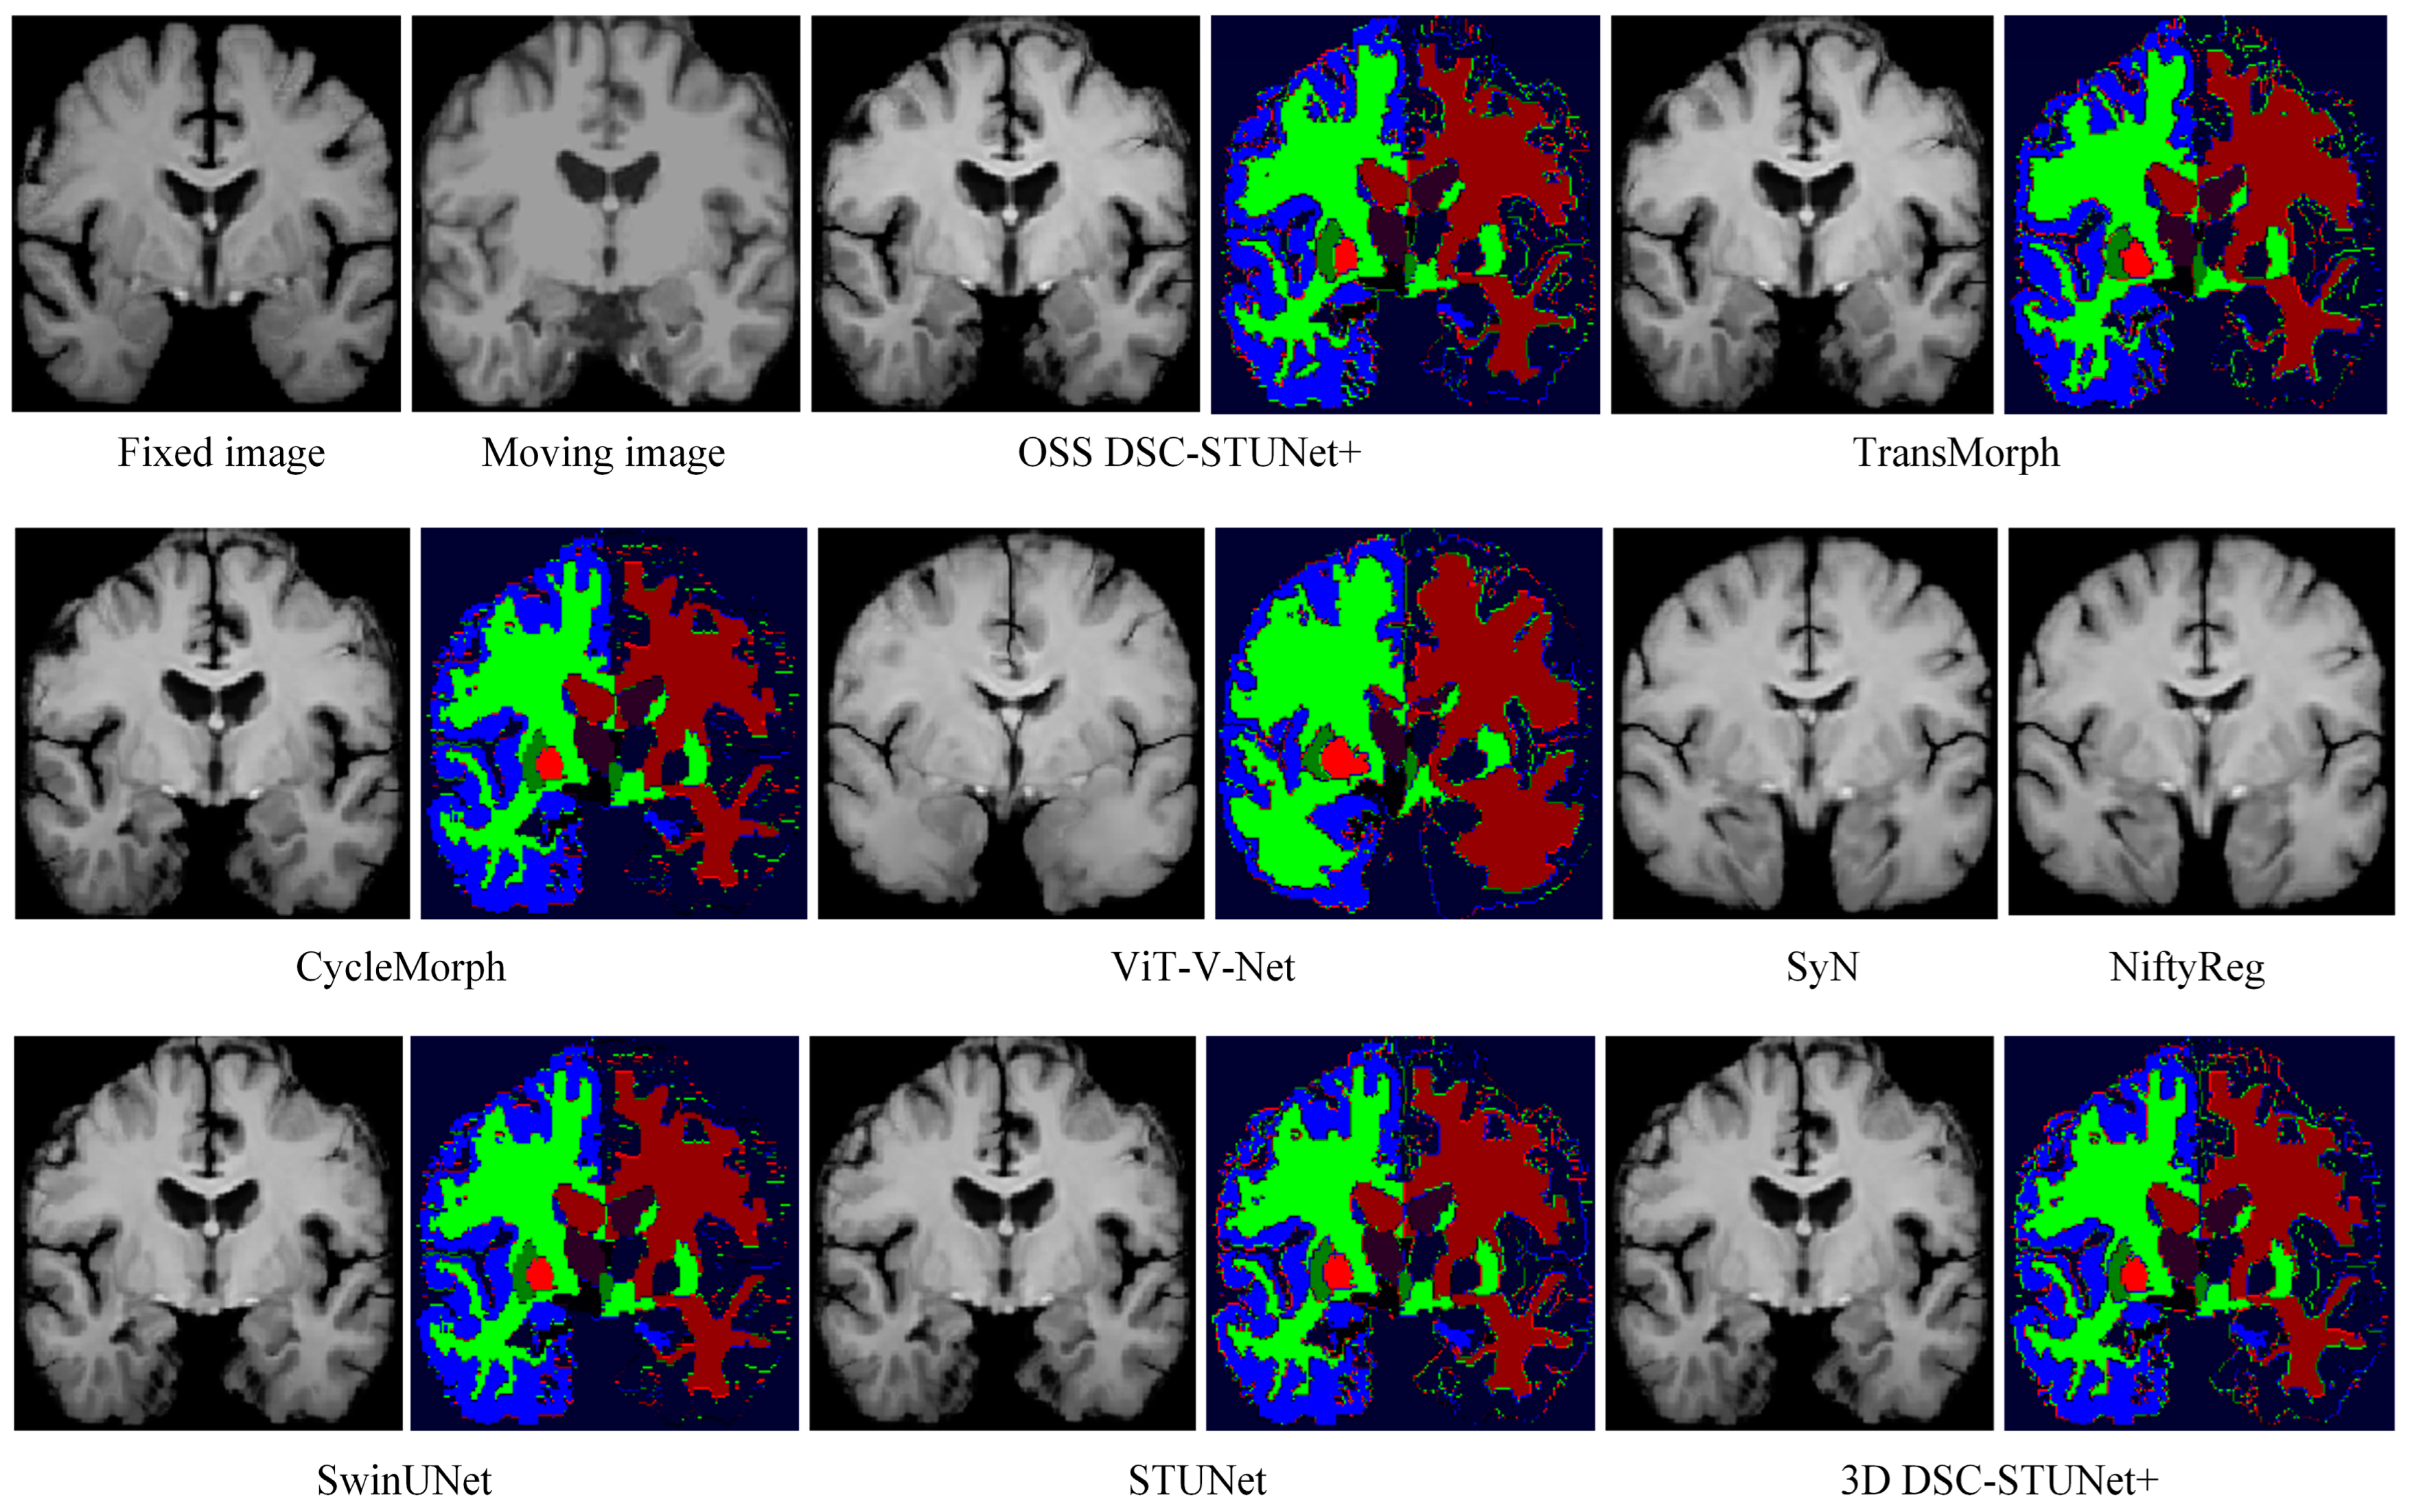

From Table 1, it can be observed that the proposed model achieved a Dice score on the IXI dataset that was 7.0% higher than CycleMorph, 6.6% higher than VoxelMorph, 16.3% higher than NiftyReg, 16.2% higher than SyN, 4.8% higher than ViT-V-Net, and 2.3% higher than TransMorph. From Table 2, the model’s Dice score on the OASIS dataset was 5.3% higher than CycleMorph, 4.8% higher than VoxelMorph, 9% higher than NiftyReg, 7.5% higher than SyN, 4.2% higher than ViT-V-Net, and 1.8% higher than TransMorph. From Table 3, on the LPBA40 dataset, the proposed model’s Dice score was 7% higher than CycleMorph, 5.9% higher than VoxelMorph, 1.1% higher than NiftyReg, 1.7% higher than SyN, 5.4% higher than ViT-V-Net, and 2.6% higher than TransMorph. Figure 7 and Figure 8 present the registration results of the different methods on the IXI dataset and OASIS dataset, respectively. From Figure 7 and Figure 8, it can be observed that the proposed method not only exceled in global accuracy compared to the conventional registration methods but also better preserved the details in the images.

In Figure 7, the feature segmentation map for the IXI dataset shows that the model demonstrated a higher level of attention to complex and irregular edges than models like TransMorph. The advantage of OSS DSC-STUNet+ over the other methods lay in its ability to extract both global and local features, which can be validated through the registration images and their corresponding feature segmentation maps.

4.3. Ablation Experiment

In order to verify the improvement in the optimization model over the training capability of the registration model and the quality of image registration, as well as to assess the enhancement in the extraction of local fine features using the 3D dynamic snake convolution and the ability of the multi-scale dense skip connection to improve the global feature extraction of the SwinUNet model, ablation experiments were conducted on the IXI, OASIS, and LPBA40 datasets. The ablation experiments used SwinUNet as the baseline network. In the OSS DSC-STUNet+ network model, the DSConv3D in the DSC-STUNet part of the registration module was replaced with Conv3D, named STUNet. Additionally, the dense skip connections in 3D DSC-STUNet+ were replaced with ordinary skip connections, named 3D DSC-STUNet. The Dice values from the ablation experiments are shown in Table 4, Table 5 and Table 6, and the result images on the IXI dataset are displayed in Figure 7.

The tables list the Dice values for the five models. The experimental results indicate that the methods proposed in this paper all improved the performance of the registration network. By increasing the depth of the SwinUNet network and the number of skip connections, the STUNet model was able to achieve a 1.5–1.7% improvement in Dice score. Replacing Conv3D with DSConv3D further improved the Dice score by 0.3–0.4%, validating the applicability of the DSConv3D module. Additionally, Figure 8 shows that the registration results of the 3D DSC-STUNet were more accurate than those of STUNet and SwinUNet, particularly in the handling of the fine white matter edges in the segmented images.

The introduction of weakly supervised learning and optimization methods into the registration model resulted in a 0.7–4.1% increase in Dice score and reduced the percentage of non-diffeomorphic voxels (|Jφ| < 0) by half. This demonstrates that OSS not only improved the model performance but also prevented the generation of overly sharpened deformation fields, which can be visually observed by comparing the actual registration results in Figure 7. In the Figure 9, we illustrates the registration results, deformation fields, and deformation grids of the OSS DSC-STUNet+ model with the application of the weakly supervised optimization strategy, compared to the 3D DSC-STUNet+ model without the weakly supervised strategy. The figure shows that the optimized deformation field captured finer details, while preserving good local details, and the global registration performance was also partially improved.

In conclusion, the analysis of the experimental results in Figure 7 confirms that introducing 3D dynamic snake convolution, utilizing multi-scale dense skip connections, increasing the model’s depth and the number of skip connections, and employing weakly supervised strategies and optimization methods during the training of deep learning models can lead to higher Dice scores in MRI image registration. The registration results were more accurate, and the model’s handling of image details was more precise, ultimately leading to enhanced model performance. These improvements demonstrate the potential of the proposed approach for tackling complex medical image registration tasks.

Figure 7. Registration results and deformation fields of different methods on the IXI dataset (z = 124).

Figure 8. Registration results and segmented images of different methods on the OASIS dataset (z = 124).